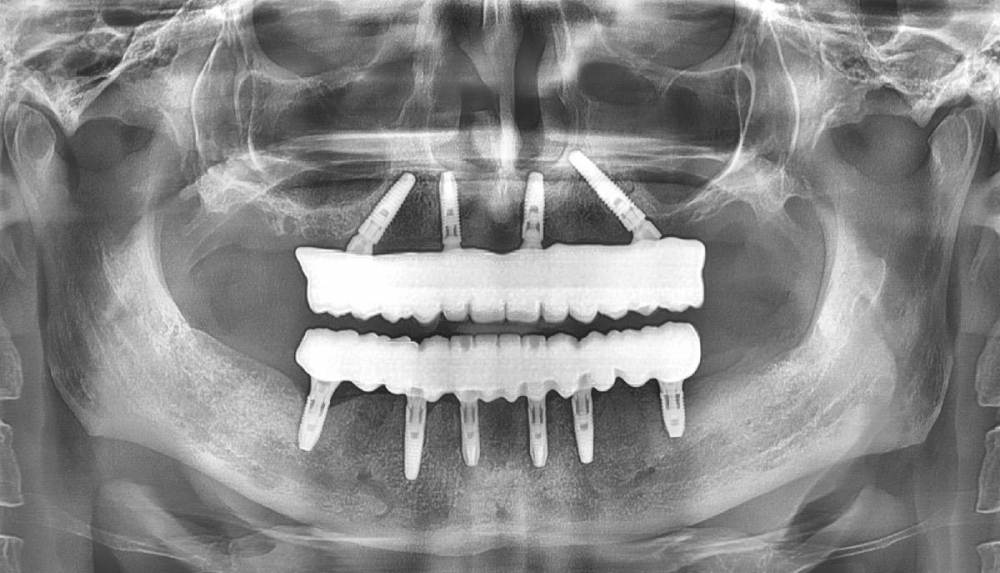

pit Опубликовано 9 августа, 2023 Поделиться Опубликовано 9 августа, 2023 Всем привет! Клинический случай тотального протезирования с опорой на имплантаты. Немедленная имплантация верхней и нижней челюсти с интервалом в 2 месяца. На верхней челюсти редукция, имплант 25 зуба транссинус. Отсроченная нагрузка, так как треснул гребень. Видео операции здесь https://youtu.be/YZM-A8we1WQ Постоянное протезирование ДЦ коронками с тирановыми каркасами. Верх с уровня МЮ, низ с уровня платформ. 2.mov 7 1 3 Ссылка на комментарий

Большой Зеленый Опубликовано 15 августа, 2023 Поделиться Опубликовано 15 августа, 2023 Петя, а чего же не 6 вверху? Ссылка на комментарий

pit Опубликовано 15 августа, 2023 Автор Поделиться Опубликовано 15 августа, 2023 1 час назад, Большой Зеленый сказал: Петя, а чего же не 6 вверху? ОСЛ не захотел пациент, а в буграх маловато кости))) Ссылка на комментарий